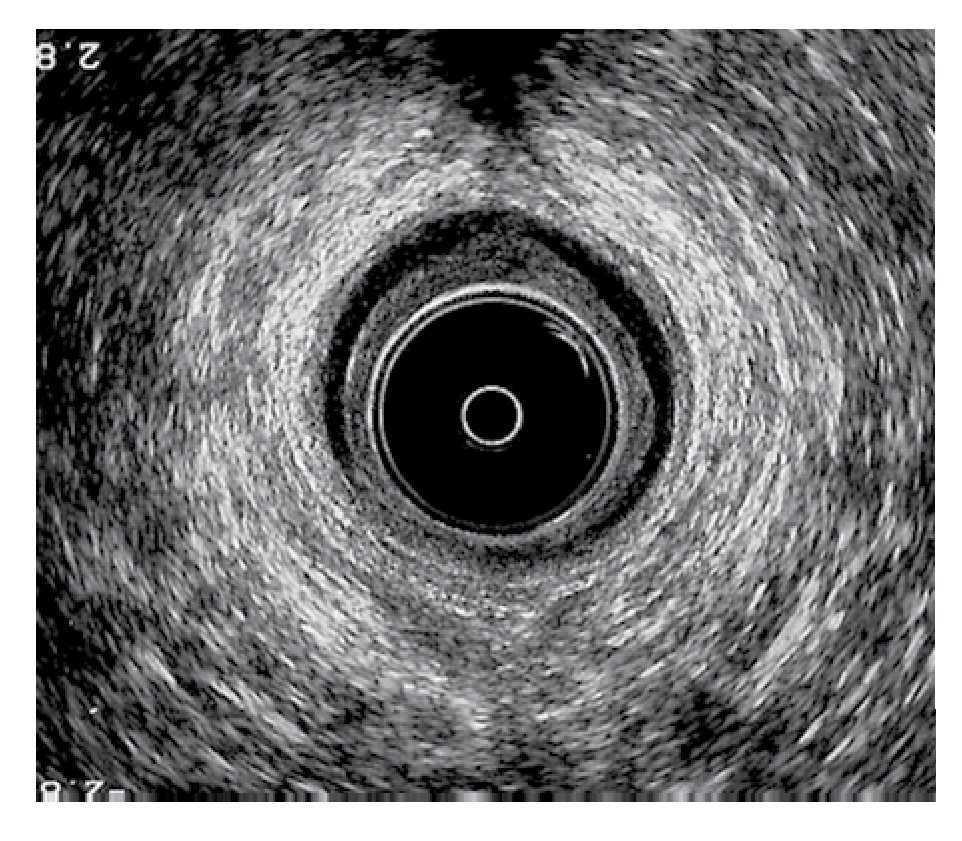

Técnica quirúrgica: Los pacientes tuvieron un lavado rectal con fosfato de sodio (Fleet enema®) una noche antes de la cirugía y una hora previa al procedimiento. Recibieron ciprofloxacino y metronidazol intravenosos previo a la intervención quirúrgica, que se realizó bajo sedación en quirófano y en decúbito lateral izquierdo, realizándose ultrasonido endoanal para identificar la lesión del esfínter interno. Después de realizar asepsia y antisepsia del área perianal con iodopovidona, se inyectaron 7.5 mL de silicón en cada paciente, con tres cartuchos de 2.5 mL cada uno (Macroplastique®), bajo guía ultrasonográfica en la zona de lesión del esfínter interno, así como en el espacio interesfintérico (Figuras 2 y 3). En total se aplicaron cuatro implantes a cada uno de los pacientes, uno en el sitio de la lesión y los otros en el espacio interesfintérico. Los procedimientos se realizaron sin complicaciones y ninguno de los pacientes presentó infección en el sitio quirúrgico.

¿Figura 2. Implante anterior derecho, lateral izquierdo y posterior colocados en el espacio inter-esfintérico y en el esfínter interno.